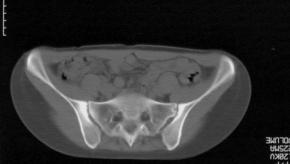

Read ArticleACR/SPARTAN Recommendations for the Treatment of Ankylosing Spondylitis and Nonradiographic Axial Spondyloarthritis

The American College of Rheumatology (ACR), in partnership with the Spondylitis Association of America (SAA) and the Spondyloarthritis Research and Treatment Network (SPARTAN), released the 2019 Update of the Recommendations for the Treatment of Ankylosing Spondylitis (AS) and Nonradiographic Axi